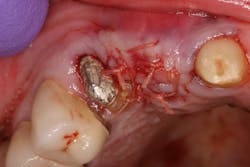

- Antiseptic mouthrinse. StellaLife has been shown to assist in tissue healing and prevent possible infections in areas of open wounds in multiple case series (figures 3–9).1